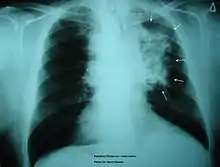

A patient's lung diagnosed with lung cancer

Asthma has been proven to have a causal relationship with smoking due to the modified inflammation reaction.[21] Alveolar macrophages will be excessively recruited onto the airway wall, leading to a narrower airway for oxygen to pass through. Some patients may also be affected by airway remodeling. Smoker's macrophages affect the elastic fibers in the mucus layer of the airways, tightening the lumen and causing asthma. Symptoms of asthma include wheezing, coughing, and chest discomfort. To ameliorate the situation, drugs that either suppress the inflammatory response or relaxes the airway will be administrated, so air can pass through.[22]